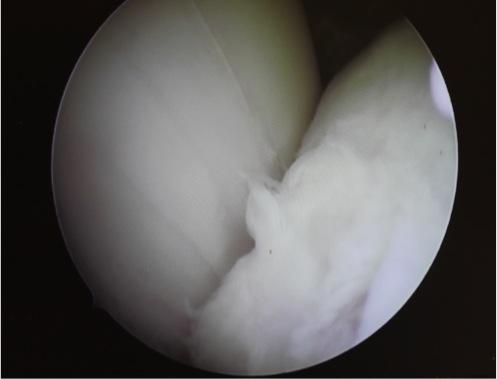

Takapolven OD- muutokset ovat tavallisia. Useimmissa tapauksissa kirurginen hoito on nuorella hevosella suositeltavaa. Optimitilanteessa röntgentutkimuksessa havaitaan muutos ilman nivelen turvotusta tai ontumaa. Tällöin ennuste on yleensä hyvä. Jos nivel turvottaa, mutta hevonen on ontumaton, on ennuste hyvä tai kohtalaisen hyvä. Jos varsa ontuu jalkaa ja nivel on turvottava, muutos on usein niin laaja-alainen, että ennuste hevosen urheilukäytölle on hyvin varauksellinen.

Nivelen sisäisellä kystalla on useimmiten ratkaiseva merkitys urheilu-uran kannalta. Tyypillisiä sijaintipaikkoja ovat takapolvi, vuohisnivel ja kehänivel. Kystan koko ja sijainti ratkaisee ennusteen.

Kystan hoito määräytyy tapauskohtaisesti. Niveleen ulottuvissa kystissa nivelen sisäinen kortisonihoito tai ultraääni- tai artroskopiaohjauksessa tapahtuva kystan sisäinen kortisoni. Jossain tapauksissa kystia on hoidettu ruuvaamalla.